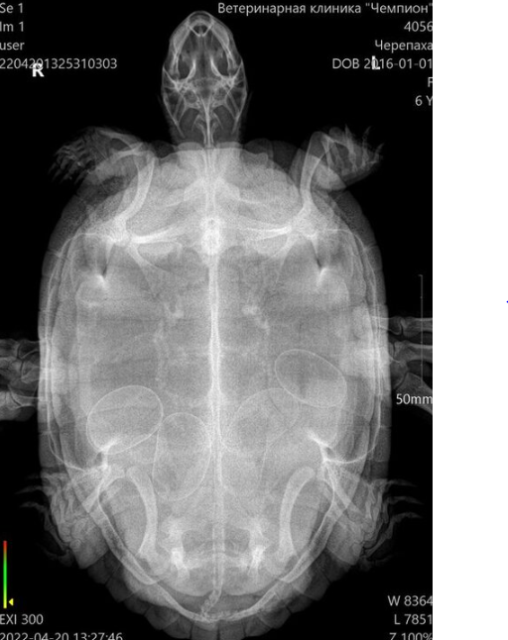

увидела снимок в личных сообщениях

снимок тут приложу, чтобы видно было

image.png.3be7faed50856f0cd6a3e0eedbe1e1a9.png

Тут нужно чтобы врач посмотрел снимок, т.к. есть яйцо неправильной формы и оценил сможет ли она сама снестись.